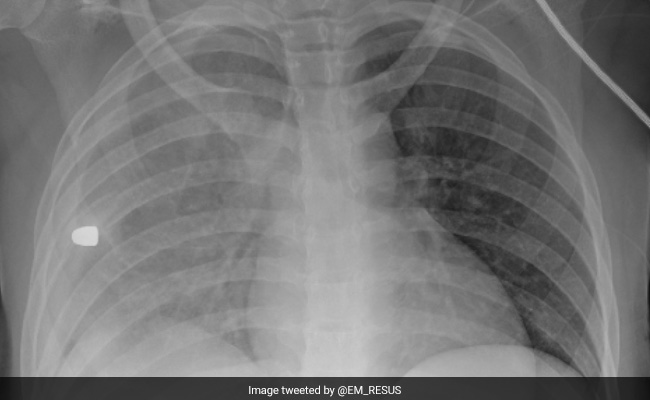

A US emergency room doctor's Twitter post about the leading cause of death among American children has gone viral. The post: an X-Ray scan of a bullet lodged in a child's chest.

"Here's the chest X-Ray of a young girl suffering from a condition that is now the #1 cause of death in children and adolescents in the US. What's the diagnosis?" Emergency Room doctor Sam Ghali captioned the image of a child's scan. The post has been liked by over seven million people.

Firearm-related injuries surpassed motor vehicle crashes in 2020 to become the leading cause of death among people aged 1 to 19 years in the United States, according to the US Department of Health and Human Services.